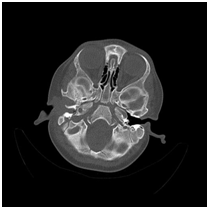

17 month old infant with complaints of right ear discharge was admitted to the pediatric clinic. Patient with a diagnosis of external otitis declared by pediatrician was started a therapy with ear drop of ciprofloxacin and dexamethasone. Patient’s complaints did not decrease despite medical therapy. Minimal swelling in the right parotid region was discovered by the patient's pediatrician so the patient was referred to our clinic with the swelling in the parotid region. At the tenth day of swelling, when pressure is applied to the patient's parotis region, it was seen that pus was drained from the parotis to the external ear canal. Thus parotid abscess was found to be drained into the outer ear canal. Cultures were obtained from the discharge. The patient underwent parotid ultrasound. In ultrasound examination, a 3 cm collection detected which was localized at the deep lobe of parotid gland and extending into the postauricular region. The patient was hospitalized. Initial laboratory tests showed a total white cell count of 7.63 K/uL and sedimentation rate was 42 mm/hr. Temporal CT findings supported the USG findings (Figure 1&2). An incision was made to the overlying skin and the abscess was drained (Figure 3). A penrose drain was placed and followed-up daily. The lesion regressed and there was no need for more radical surgery. Staphylococcus epidermidis which was resistant to most of antibiotics was isolated on culture. Teicoplanin at 10mg/kg/dose was added to treatment protocol. Ten days of antibiotic therapy resulted in complete recovery and the patient was discharged. The first follow-up visit took place within 1 month and he was symptom-free except a scar tissue where the abscess was drained.

Figure 1 Right parotid abscess seen in CT scan.

Figure 2 Abscess extending into external auditory meatus.